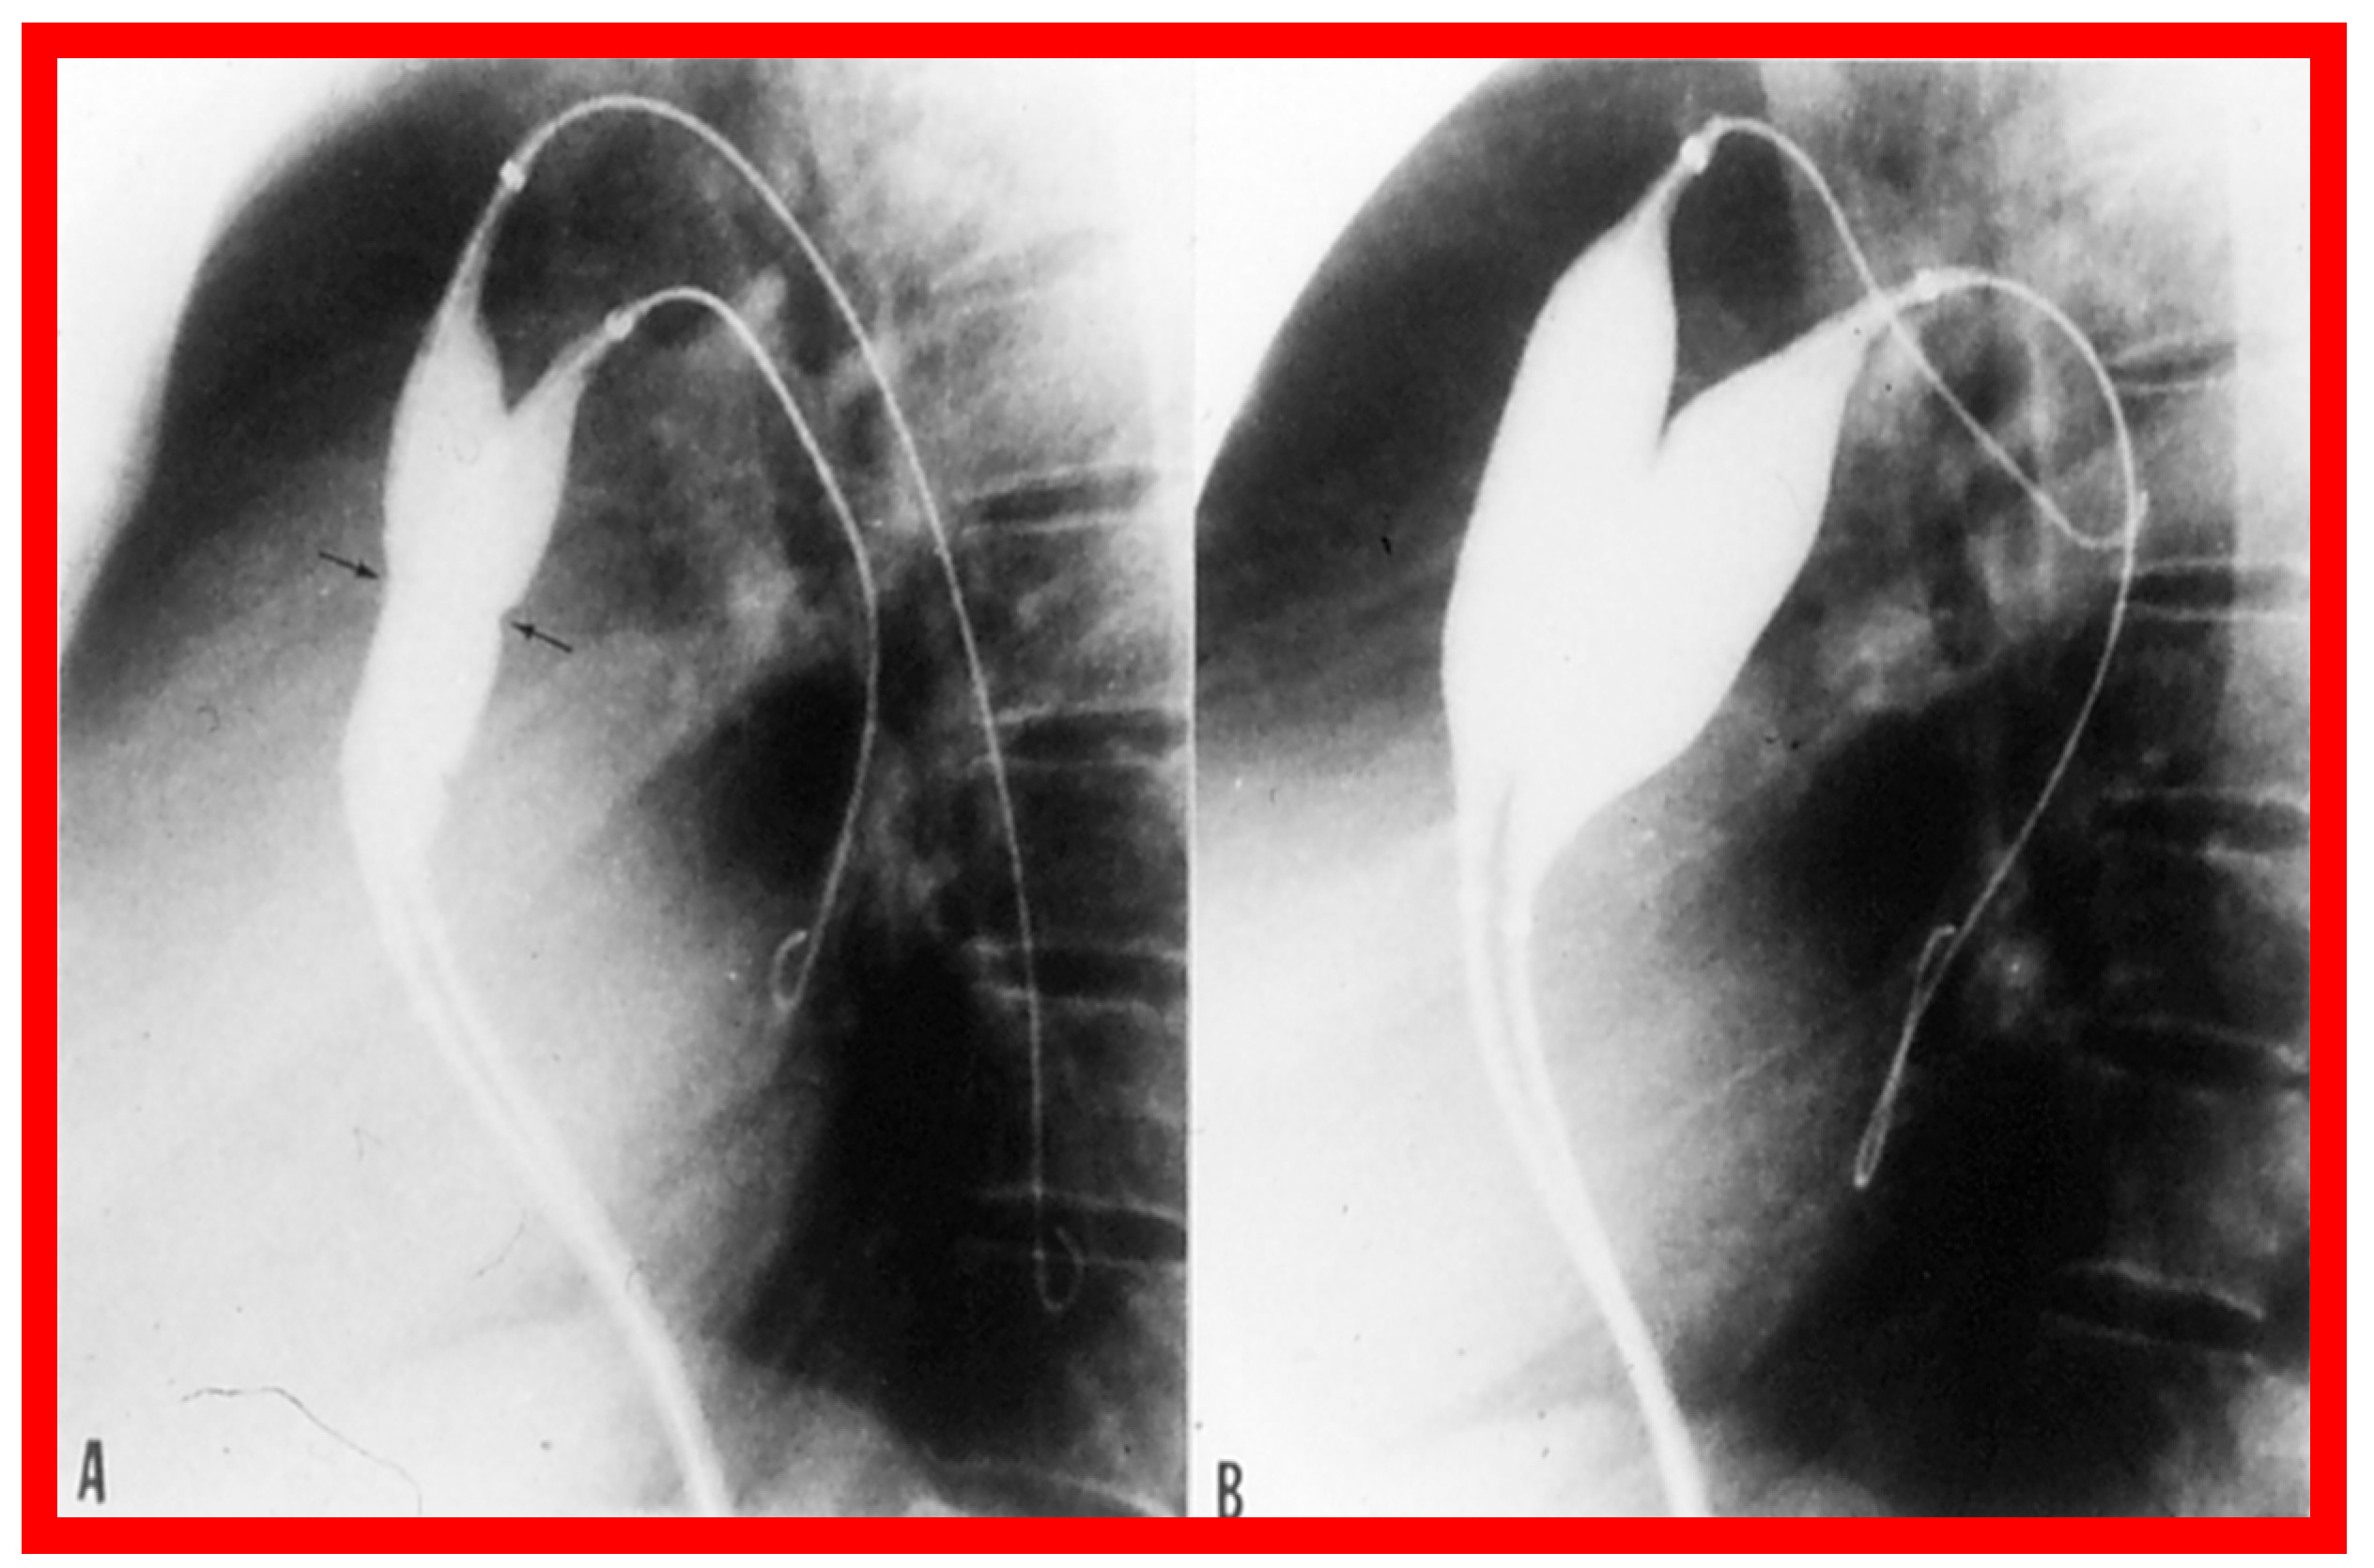

3.2. Aortic Stenosis

Aortic Stenosis in the Fetus